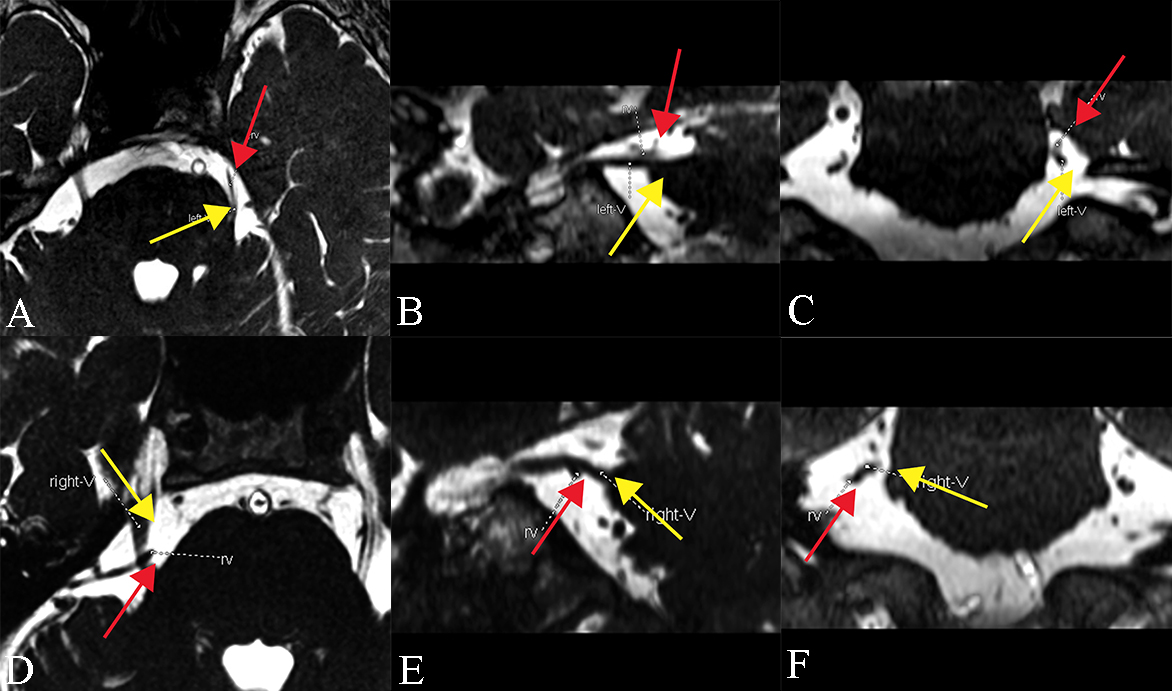

The system has four degrees of neurovascular contact assigned with score 0–3. Score 0 refers no relationship between the nerve and the vessel, or the relationship is difficult to be evaluated. Score 1 is marked by vessel crossing or touching the nerve without any root deformity and celebrospinal fluid. A significant indentation on the trigeminal nerve root caused by the compression of the offending vessel could be defined as Score 2. An existence of a distortion and/or a displacement of the compressed root, compared with the asymptomatic side should be identified as Score 3, the most severe one. Besides, the overall NVC score is calculated in the sum of three scores assessed separately from axial, oblique sagittal, and coronal planes. The assessment illustration is seen in Fig. 1.

Fig. 1.NVC score assessment illustration. Upper panel: 3D-FIESTA with axial (A), oblique sagittal (B), and coronal (C) images of a 68-year-old female: the NVC score of (A), (B), and (C) were 1, 1 and 1, respectively. The overall NVC score of this patient was 3. Lowe panel: 3D-FIESTA with axial (D), oblique sagittal (E), and coronal (F) images of a 60-year-old female: the NVC score of (A), (B), and (C) were 3, 3 and 3, respectively. The overall NVC score of this patient was 9; yellow arrow: trigeminal nerve; red arrow: offending vessel (NVC, neurovascular compression; FIESTA, Fast Imaging Employing Steady-state Acquisition).